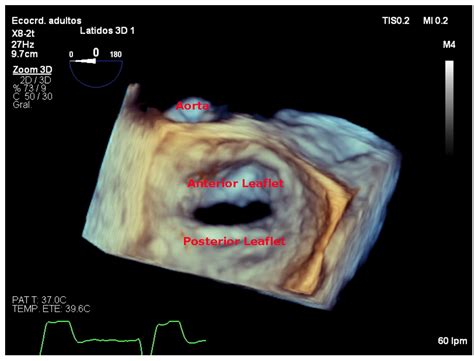

An echocardiogram, or *echo*, is a non-invasive diagnostic test that uses high-frequency sound waves to produce images of the heart. This procedure is invaluable in diagnosing and monitoring mitral stenosis. During a *mitral stenosis echo*, the ultrasound waves bounce off the heart's structures, creating detailed images that can be analyzed by a cardiologist.

• Transesophageal Echocardiogram (TEE): In this procedure, the ultrasound probe is inserted down the throat and into the esophagus, providing clearer images of the heart's structures, especially the mitral valve.

Valve Morphology: The shape and structure of the mitral valve are examined to determine the extent of narrowing and any signs of calcification or thickening.